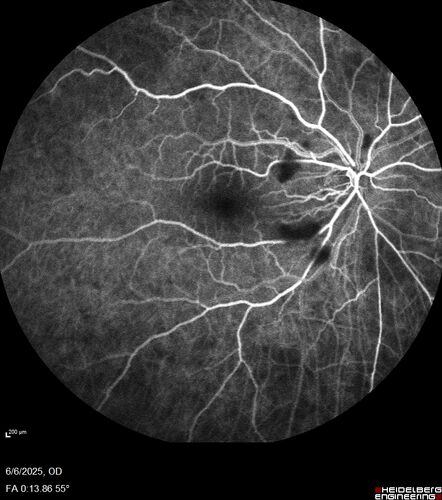

Cotton Wool Spots following cardio-pulmonary bypass

The patient had emergency thoracotomy about 3 weeks ago he had an aortic dissection with a root aneurysm. It had dissected down to the iliacs. The patient had a thoracotomy and aortic valve replacement and large aortic graft.